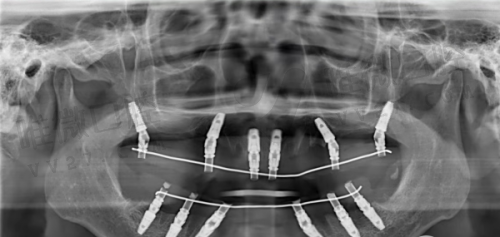

拜伦口腔是国内连锁牙科品牌,在多个城市设有分支机构,罗定店作为其布局中的一环,秉持统一医疗标准。该店设有夜诊服务,便于上班族和学生错峰就诊。具备CBCT影像系统、种植导航设备,提升治疗的可视化和精细度。在种植牙领域有All-on-4、穿颧种植等精良方案。

进口种植牙8500-13800元/颗,隐形矫正20000-38000元,金属托槽矫正6500元起。